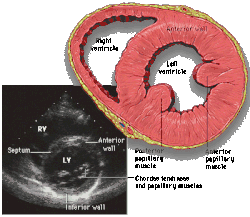

Parasternal short axis (PSAX)

Parasternal short axis at mid-LV showing papillary muscles

Parasternal short axis showing aortic valve

This view is obtained in the same window as the parasternal long, but with the probe rotated 90°. In this view, the aortic valve is seen in cross-section with the right ventricular inflow & outflow tracts visible with the tricuspid valve as well. Pulmonary valve is not visible in this view. Both the right and left atria are visible.

The standard PSAX view is at the level of the aortic valve, but moving the probe along the long-axis can review the LV outflow tract, LV at the base, and LV at the midsection.

Structures visible:

• Aortic valve in short-axis

• Aortic valve dysfunction, aortic sclerosis/stenosis

• Tricuspid valve in long-axis

• Pulmonary valve in long-axis

• Right ventricle, including inflow and outflow tracts

• Left ventricle in short-axis

• Closer to the base can reveal the left ventricular outflow tract

• At the level of the base can show the movement of the mitral valve leaflets in short-axis

• At the level of mid-LV can show papillary muscles

Measurements in this view can be used to quantify the heart:

• Aortic valve area by planimetry

• Color doppler of all four valves

• Spectral doppler of tricuspid and pulmonary valves